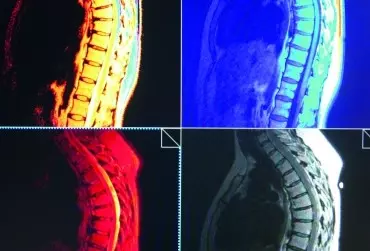

Diagnostyka różnicowa odcinka piersiowego kręgosłupa i klatki piersiowej - część 2

Ból pojawiający się w obrębie odcinka piersiowego kręgosłupa i klatki piersiowej może stanowić skutek dysfunkcji kręgosłupa, ale jego przyczyną mogą być też inne poważne schorzenia, w tym nowotwory, złamania osteoporotyczne. Dlatego tak bardzo ważna przed wdrożeniem leczenia jest prawidłowa diagnostyka różnicowa, obejmująca dokładne badanie kliniczne oraz badania obrazowe.

Diagnostyka różnicowa odcinka piersiowego kręgosłupa i klatki piersiowej - część 1

Piersiowy odcinek kręgosłupa stanowi najsztywniejszy odcinek szkieletu osiowego ze względu na połączenie z żebrami i mostkiem.

Z uwagi na ścisłą współzależność układu nerwowego somatycznego i autonomicznego w jego obrębie konieczne jest różnicowanie dolegliwości bólowych odczuwanych przez pacjenta w okolicy klatki piersiowej z bólami pochodzenia ściennego i trzewnego. W artykule omówiono anatomię i biomechanikę piersiowego odcinka kręgosłupa oraz obrazowe metody diagnostyczne umożliwiające ustalenie prawidłowego rozpoznania.